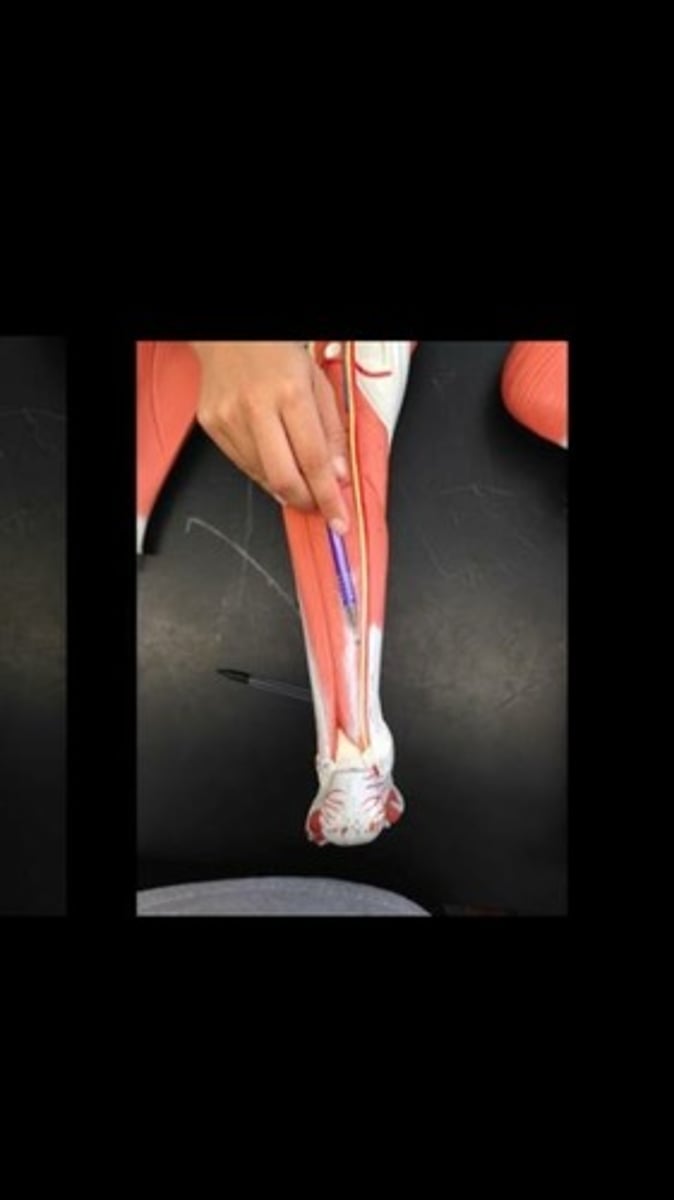

Flexor digitorum longus

Flexor hallucis longus